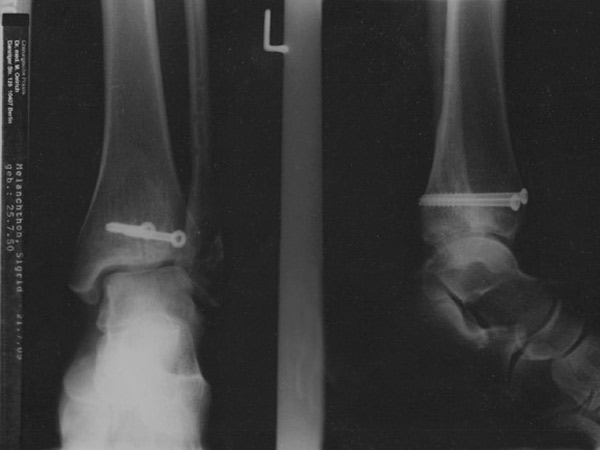

Diese beiden letzten, V-förmig von vorn nach hinten durch den Knöchel reichenden Schrauben werden am 28.07.2009 nach dem Seenland 100 - ein Jahr nach dem Unfall am 26.07.2009 - entfernt. Die Straße mit der tückischen Schiene wurde weggesprengt, um einen Verbindungskanal zwischen zwei Seen zu schaffen. Und das ist gut so! |